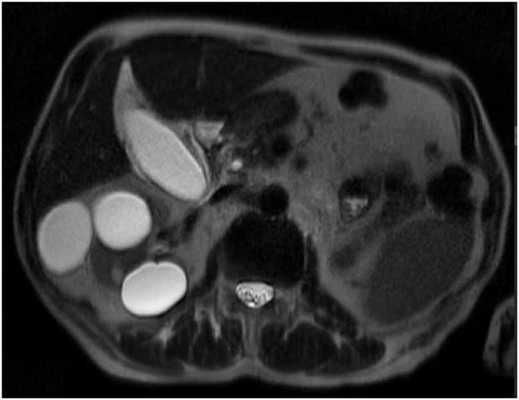

![МРТ брюшной полости]()

МРТ брюшной полости. На МР-томограмме в аксиальной плоскости отмечается увеличение размеров селезенки, МР-сигнал от селезенки однородный, структура селезенки не изменена (серый МР-сигнал на представленном изображении справа).